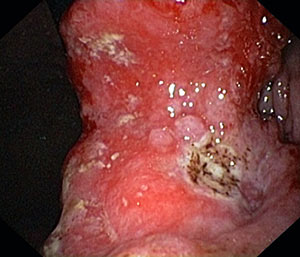

Tumori maligni dello stomaco. Sono tra i più frequenti tumori insieme a quelli del colon-retto, dei polmoni e della mammella. A seconda del tipo istologico vengono distinti in:

Gastroscopia con biopsia

Nel caso di tumore maligno in fase iniziale esso può essere asportato con la mucosectomia endoscopica. Se il tumore è in fase avanzata intervento chirurgico.